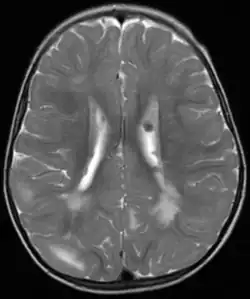

Fehlbildungen und Tumoren des Gehirns werden oft frühzeitig festgestellt. Kortikale glioneuronale Hamartome, die so genannten Tubera (Vorwölbungen) im Bereich der Hirnrinde, gehen häufig mit Epilepsie einher und können kognitive Beeinträchtigungen verursachen, während subependymalen Riesenzellastrozytome und subependymale Knötchen aufgrund ihrer Nähe zum Ventrikelsystem typischerweise zur Entwicklung eines Hydrozephalus führen.